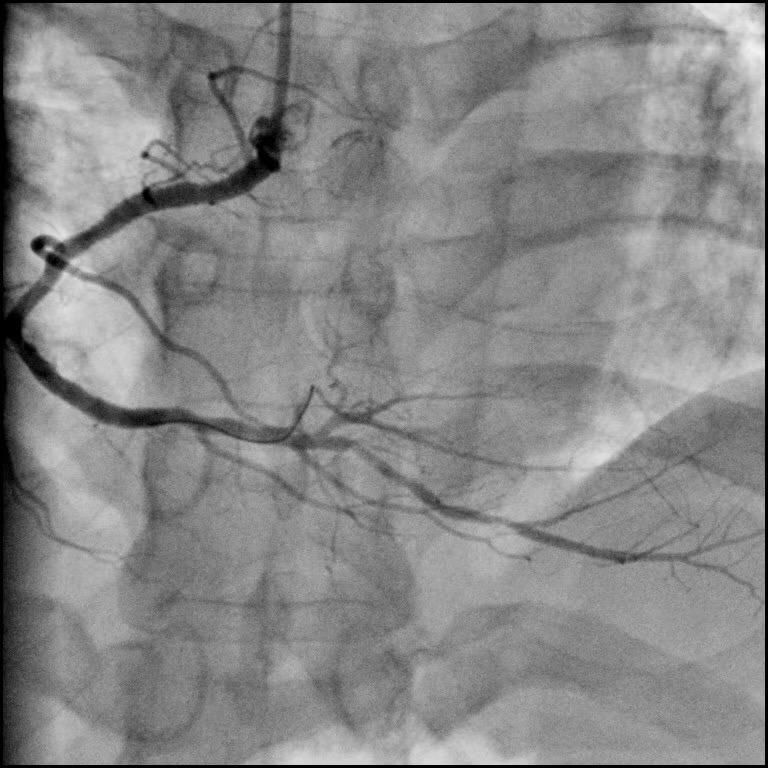

血管造影術(shù),精準診斷疾病

極光平板DSA冠脈造影-大C-唯邁醫(yī)療

經(jīng)外周血管穿刺引入導管,經(jīng)導管向血管內(nèi)注入對比劑使血管內(nèi)腔顯影以診斷血管疾病, 是診斷血管病的 “金標準”。 根據(jù)導管進入血管的部位和深度分為 3 類:

選擇性血管造影

大血管的一級分支血管造影,用于整體性顯示某一臟器或某一區(qū)域供血,顯示病變、病變的病理血管、病變與正常血管的關(guān)系等。

超選擇性血管造影

大血管的二級或二級以上分支血管造影,用于直接顯示器官內(nèi)的病變、病變的血管構(gòu)造。有心臟造影、動脈造影、靜脈造影和淋巴管造影等。